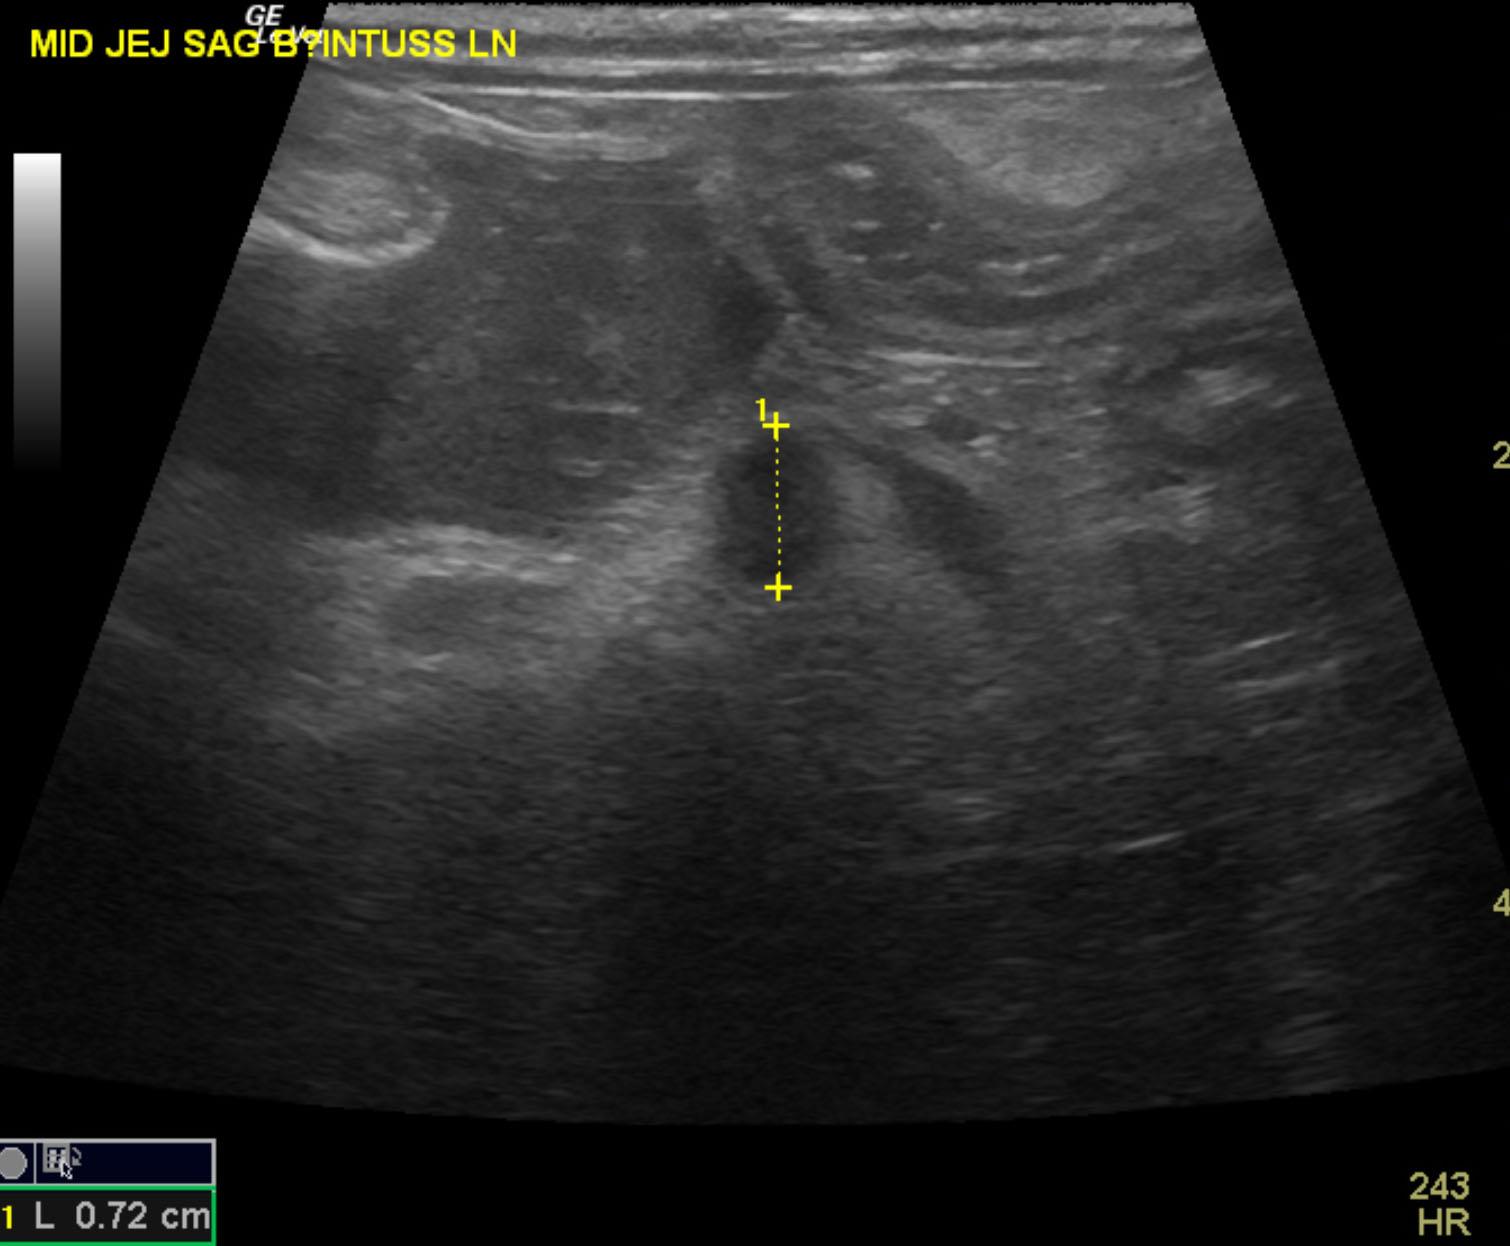

The patient is a 13 year old spayed female Dachshund dog which was presented for four days of anorexia and vomiting. She was given Cerenia, which helped, but still had ileus. Dog has vomited carpet material in past. Spec cPL was normal. Radiographs revealed dilated intestine, which appeared to be colon and cecum.